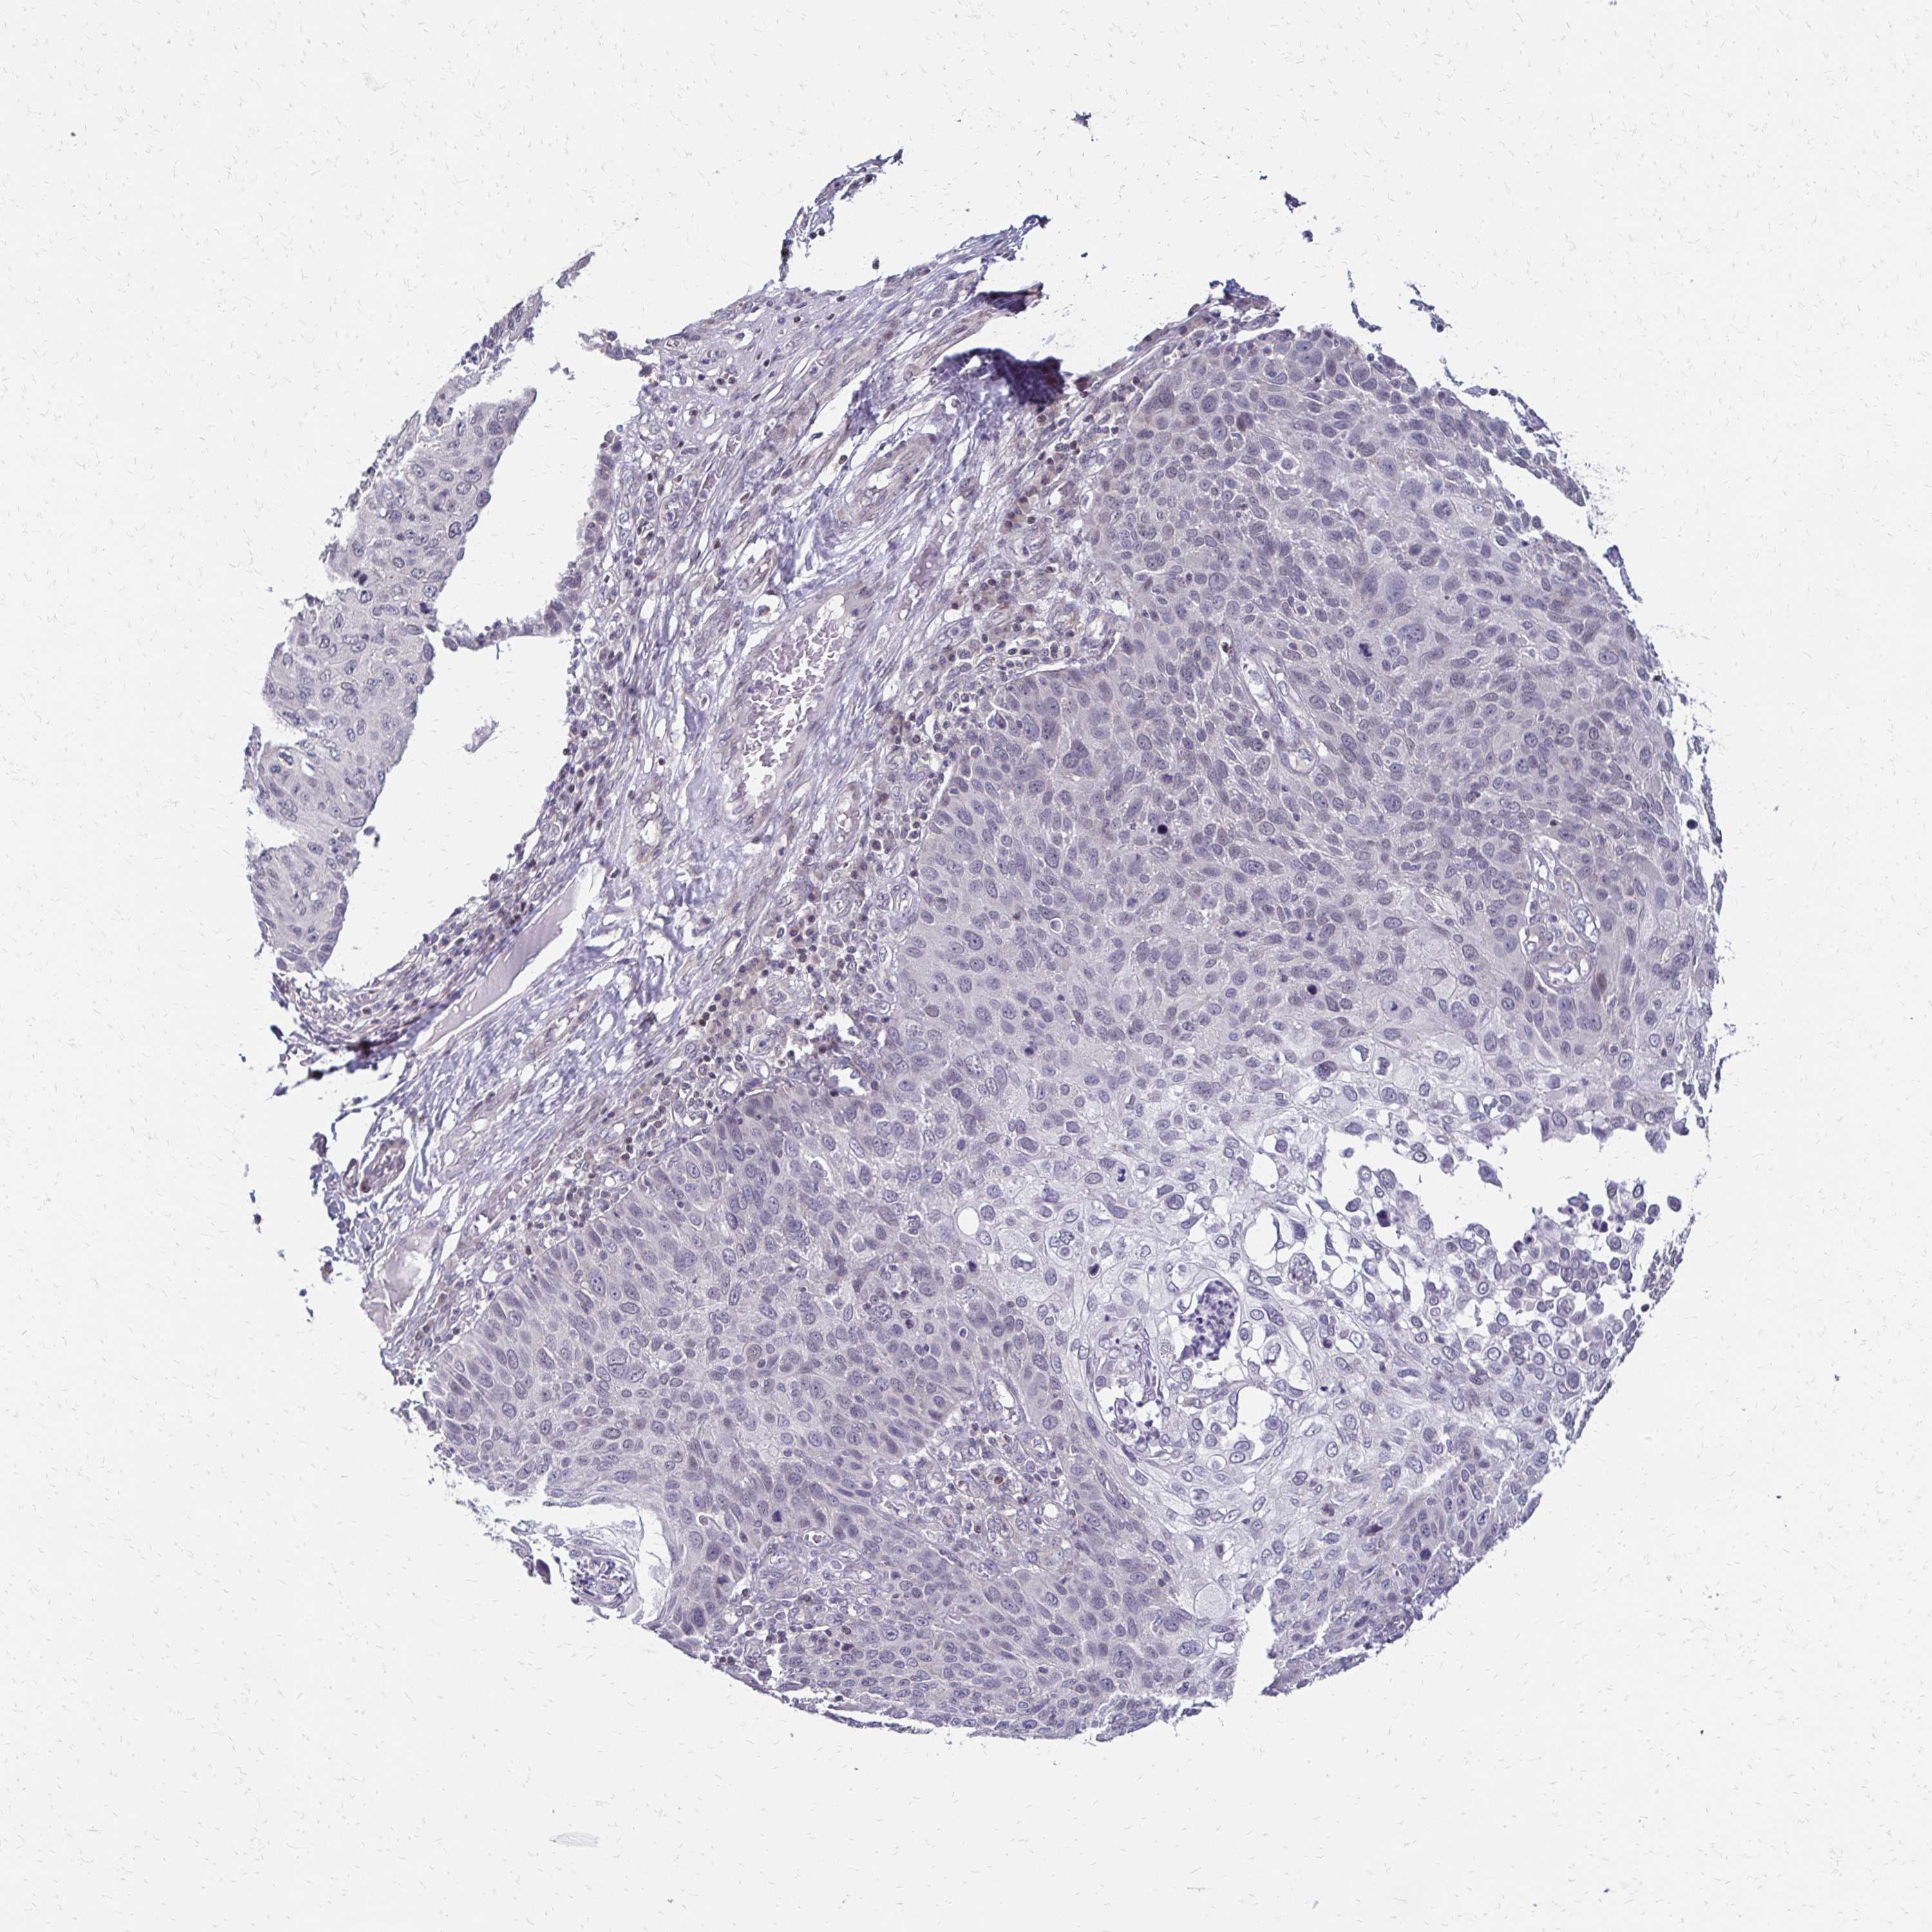

SKIN CANCER - Protein expressioni

A mouse-over function shows sample information and annotation data. Click on an image to view it in a full screen mode. Samples can be filtered based on level of antibody staining by selecting one or several of the following categories: high, medium, low and not detected. The assay and annotation is described here.

Each image is clickable and will lead to virtual microscopy that enables deeper exploration of all samples and also displays staining intensity scores, fraction scores and subcellular localization as well as patient and tissue information for each sample.

Antibody CAB011574

Squamous cell carcinoma, NOS